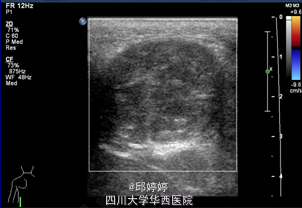

患儿,男,3岁。发现左侧臀部包块2月余。无发热,疼痛,黄疸,乏力、恶心、呕吐、腹痛、腹泻等表现。精神,饮食,睡眠,体重,大小便均无明显异常。

查体:左侧臀部近骶尾部触及一包块,大小约4x3cm, 边界清楚,形态较规则,质地较软,可活动,无压痛,无充血,水肿。腹股沟淋巴结未触及。双下肢肌力及运动功能未见异常。血清肿瘤标志物正常。 超声:左侧臀部近骶尾部皮下查见弱回声团,大小约40x34x33mm,边界清楚,形态规则,内部回声不均匀,内未见明显血流信号。 超声诊断:左侧臀部近骶尾部皮下弱回声团:畸胎瘤?

手术切除。术后病理诊断:<骶尾部>囊性成熟性畸胎瘤。